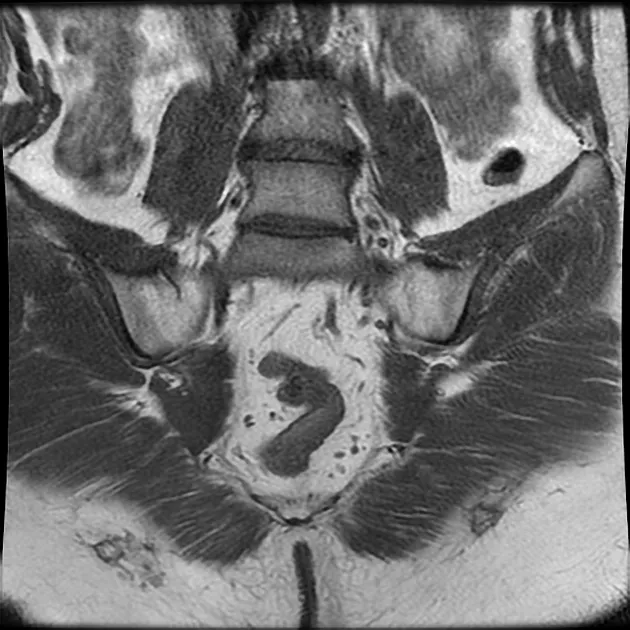

MRI SI Joints

The sacroiliac joints, which connect the central sacrum bone to the ilium bones of the pelvis on either side, are seen in an MRI scan of the sacroiliac joints.